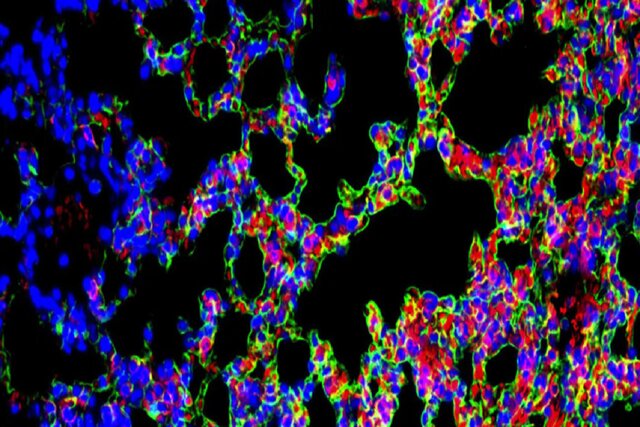

مشخص نیست که چه چیزی فیبروز ریوی ایدیوپاتیک را ایجاد میکند اما پیشروی بافت زخم، در نتیجه فعالیت غیرعادی سلولهای اپیتلیال در ریهها رخ میدهد. این سلولها که مانند یک رابط میان محیط و بدن عمل میکنند، در آغاز واکنشهای ایمنی دخیل هستند و به ترمیم زخم کمک میکنند.

در بیماران مبتلا به فیبروز ریوی ایدیوپاتیک، سلولها آسیب میبینند و تولید مقادیر زیادی از کلاژن و پروتئینهای خارج سلولی را آغاز میکنند که به ایجاد زخم در ریهها منجر میشوند. یک راهبرد درمانی موثر مستلزم آن است که هم ماتریس خارج سلولی اضافی پاک شود و هم سلولهای اپیتلیال آسیبدیده به حالت سالم بازگردانده شوند.